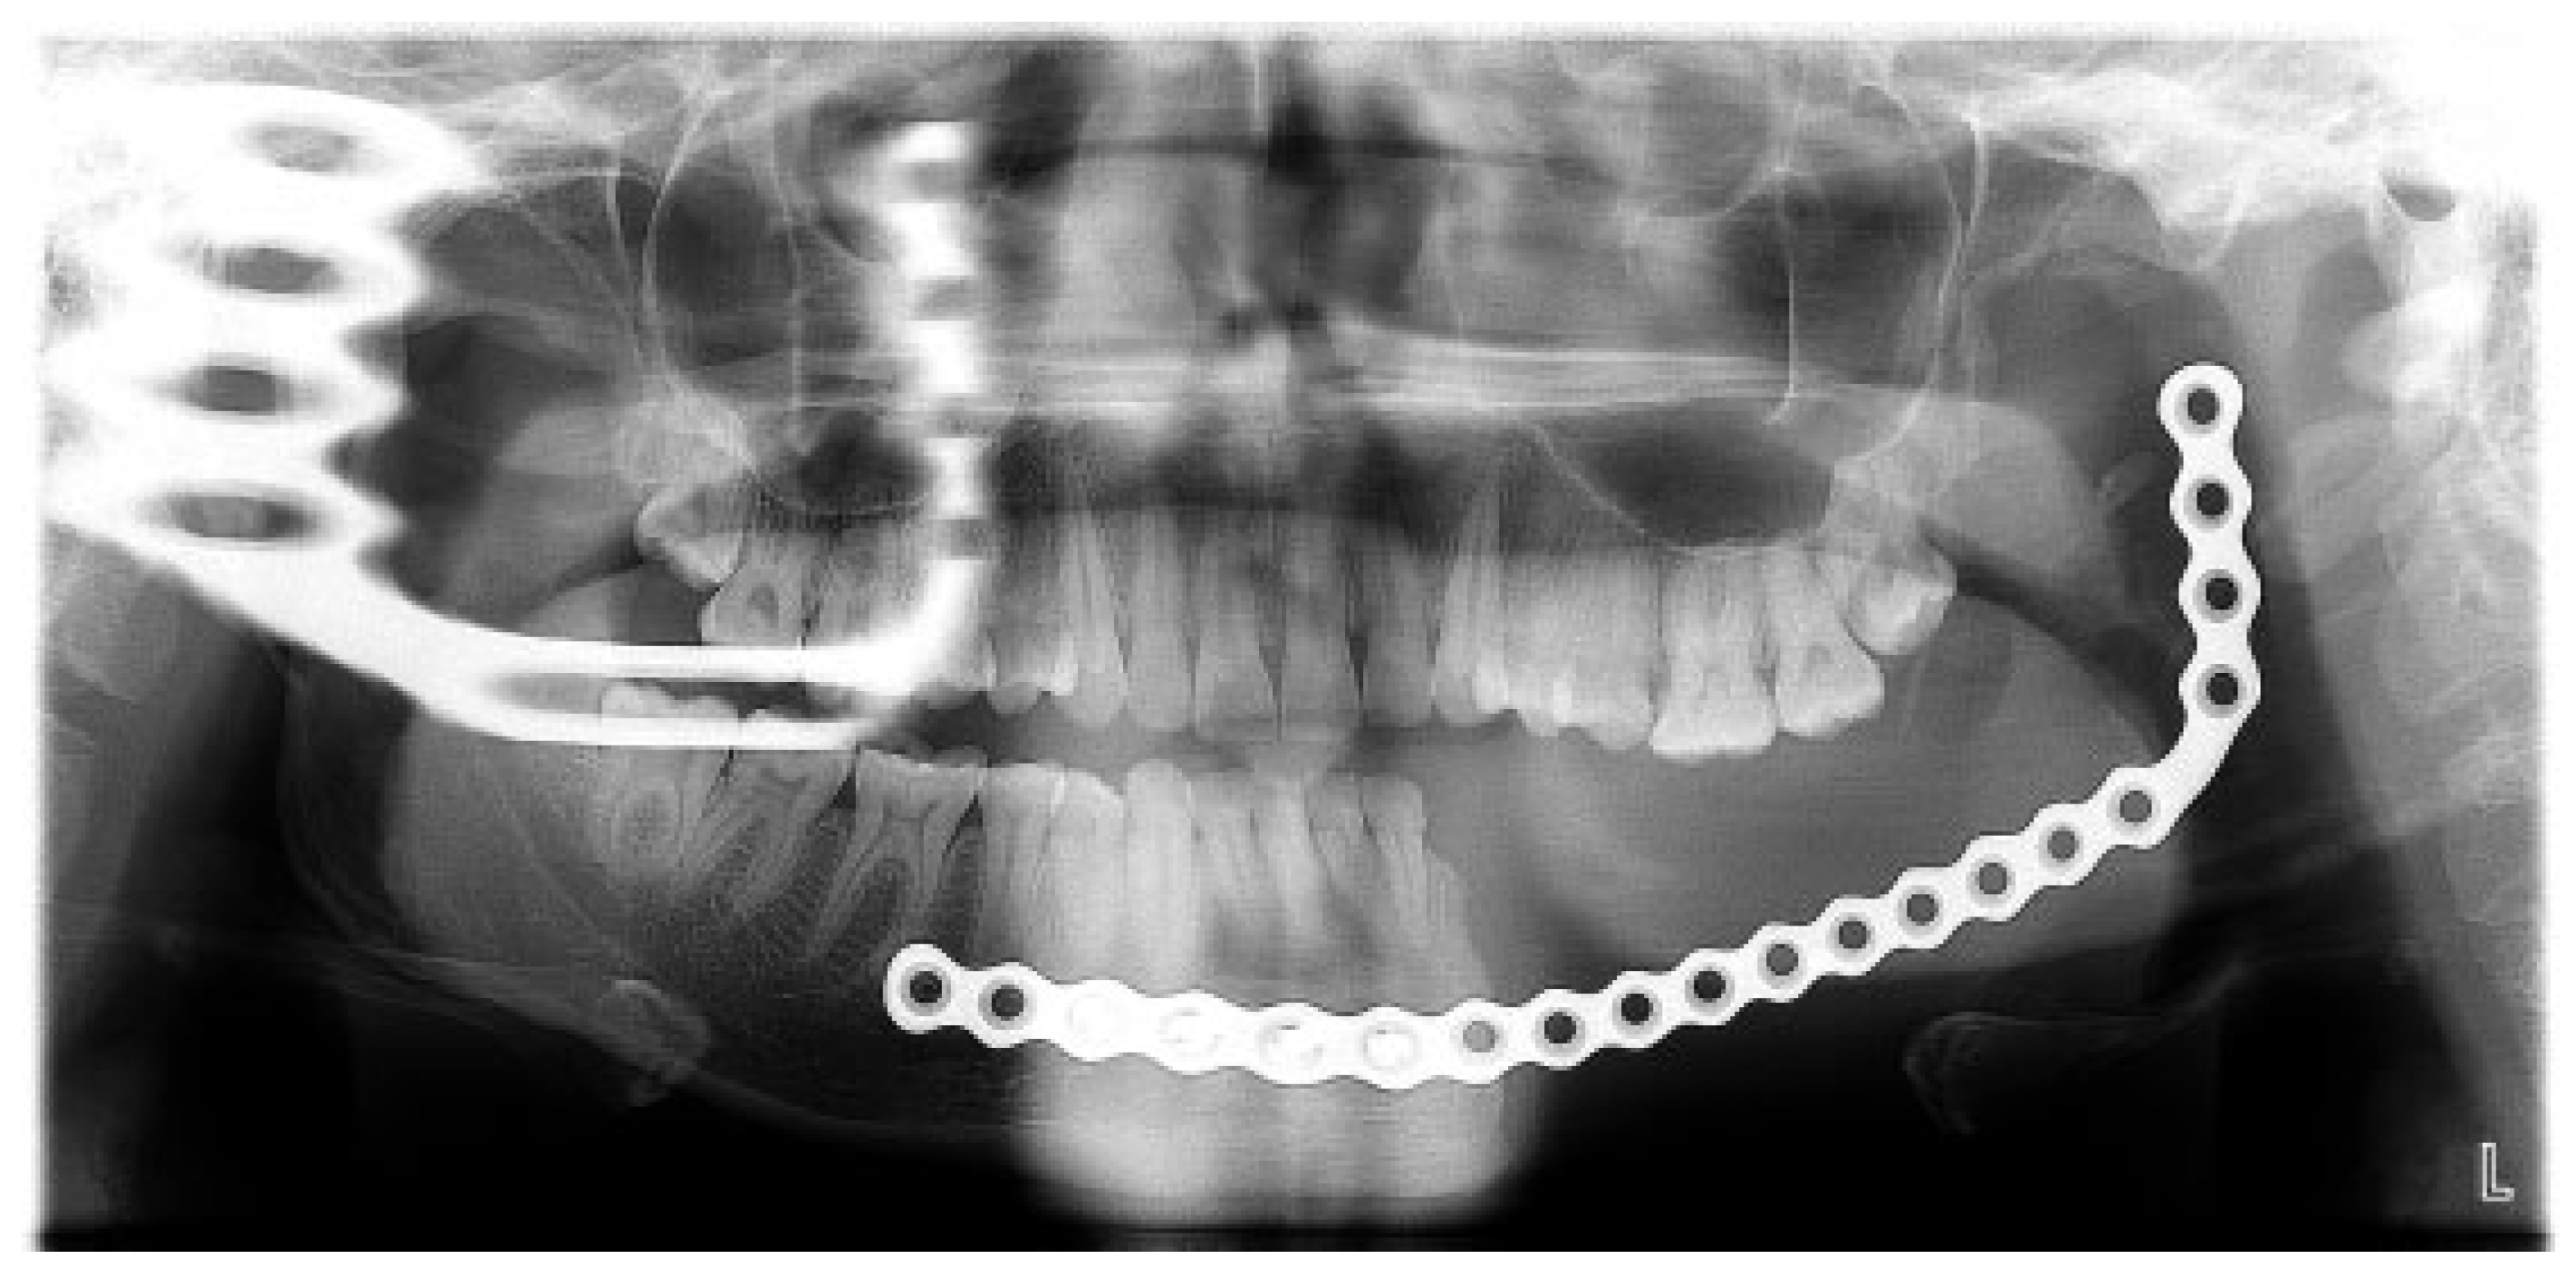

Figure 15.

Case 2. Orthopantomogram view showing the formed regenerate post consolidation.